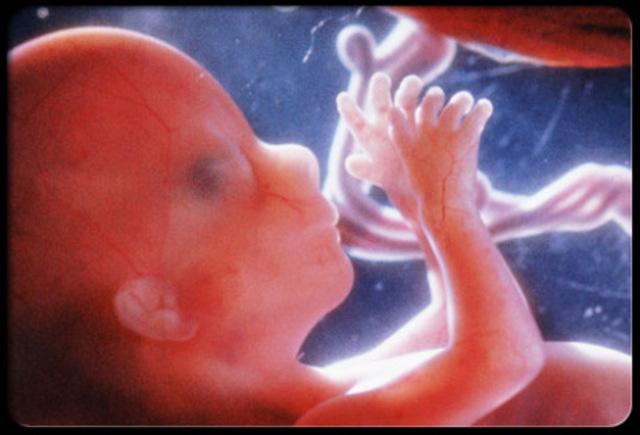

• Prenatal- Fetus able to Hear

Prenatal- Fetus able to Hear

At 18 weeks the fetus develops the inner ear and is able to hear! This is still in the fetal stage. Now that the unborn child is able to hear its mother and father they become familiar with their voices. They will even have preference to their mother and parents because that is the voices they have heard usually most often. This image shows a fetus’ ear.

Image from Google image